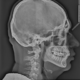

Как стоматолог, рекомендую проверить пятый зуб на верхней челюсти, похоже не запломбирован один из корневых каналов и пломба имеет поднутрнения со стороны шестого зуба, а так подозрение на кариес седьмого зуба в пришеечной области в межзубном промежутке со стороны шестого зуба

Да, правда- что за кружочек по центру? Так череп крепится к позвоночнику или что? Шарнирное соединение какое то?